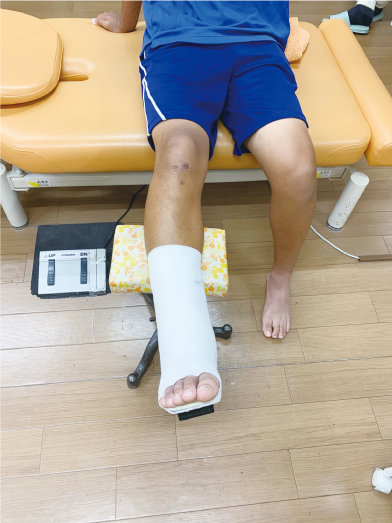

骨折/足趾骨骨折

整復後

固定